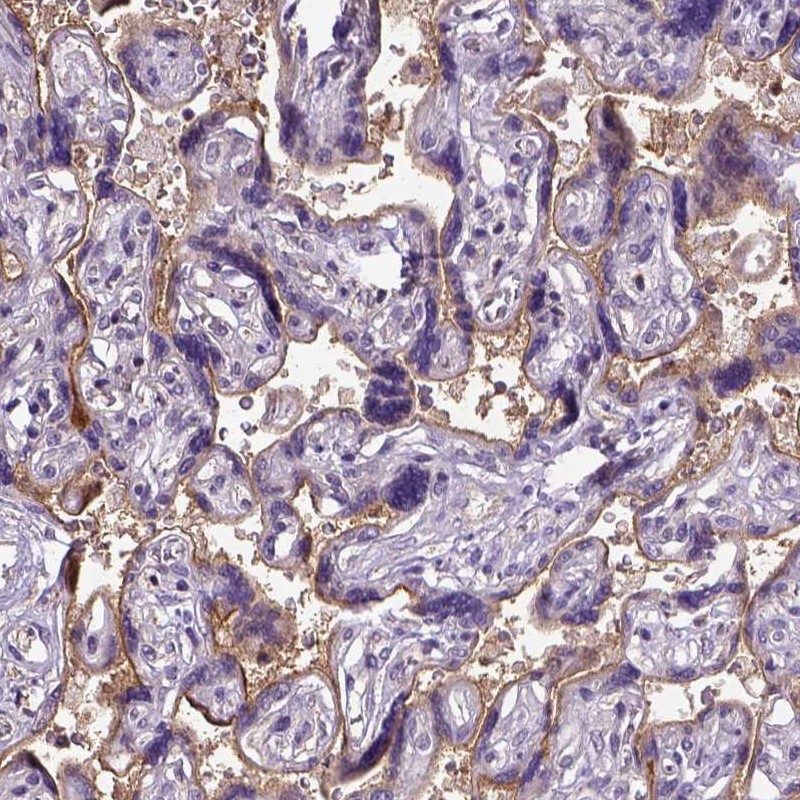

Immunohistochemical staining of human placenta shows moderate membranous positivity in trophoblastic cells.